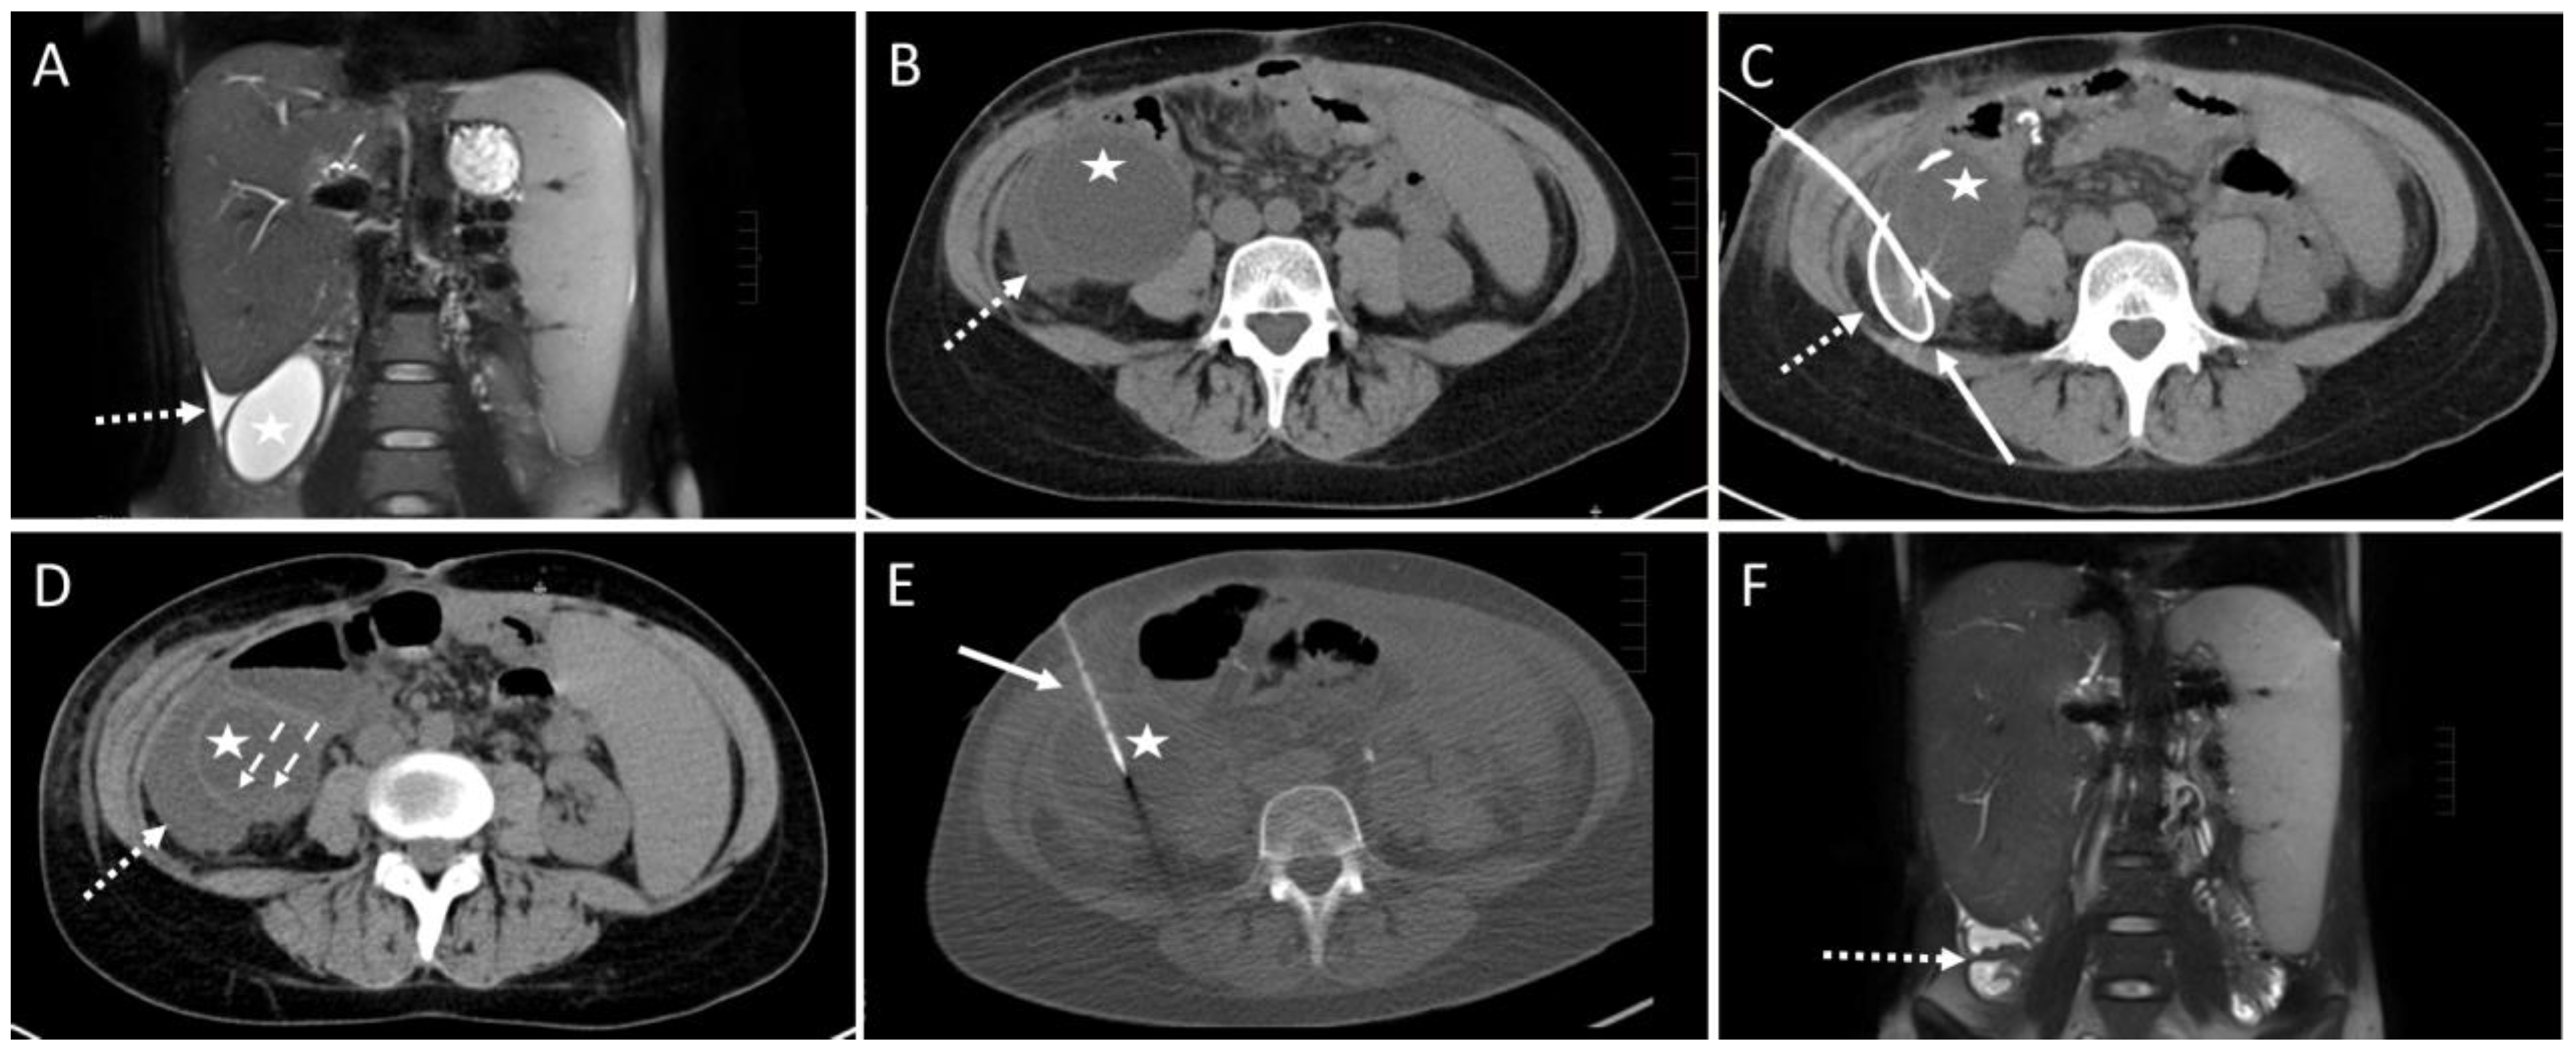

Figure 3. Example of a CT-guided drainage placement involving minor complications in accordance with SIR (Society of Interventional Radiology) guidelines. A 30-year-old female with a history of liver transplantation due to primary sclerosing cholangitis. Postoperative ultrasound follow-up revealed a cystic subhepatic fluid collection that recurred over months and was considered to be a biloma. The patient was symptom-free. However, approximately 10 months after transplantation the patient complained of increasing feeling of pressure and pain in the right lower quadrant of the abdomen. (A) MRI scan (coronary reconstruction) revealed a roundish thin-walled fluid collection (asterisk) in the subhepatic paracolic gutter, which, in the context of the described symptoms, was an indication for elective CTD. Additionally, note the small amount of ascites in the perihepatic and perisplenic gutter (dotted arrow). (B) Pre-interventional CT planning scan shows the cystic fluid collection (asterisk) and the surrounding ascites (dotted arrow). (C) Post-interventional control scan: Due to a highly rigid wall an 8F drain (solid arrow) could only partially be inserted via the Seldinger technique. The proximal end is dislocated in the right subhepatic gutter (dotted arrow). (D) Post-interventional unenhanced CT control scan after partial aspiration and removal of the drain exhibits a small hemorrhage (dashed arrows, density: 22 Hounsfield units) at the bottom of the cavity of the cystic formation (asterisk). Further, a slight increase in the extent of the fluid collection (dotted arrow, compare to figure (B)) in the gutter was observed, most probably due to fluid loss through the drain access hole into the gutter. Microbiological analysis was negative. (E) CT fluoroscopy: After 4 weeks, a new approach using the Trocar technique was attempted and a successful drainage placement was obtained. Asterisk: cystic fluid collection. Arrow: 8F drain. However, 6 months later, due to recurrence of the fluid-filled collection with vena cava compression, the formation was operatively resected. Histopathological examination revealed a cholangiocele of the bile duct system. (F) Postoperative MRI scan 4 month after surgery shows only parts of colon and small amounts of ascites subhepatically (dotted arrow) at the original site of the cholangiocele.